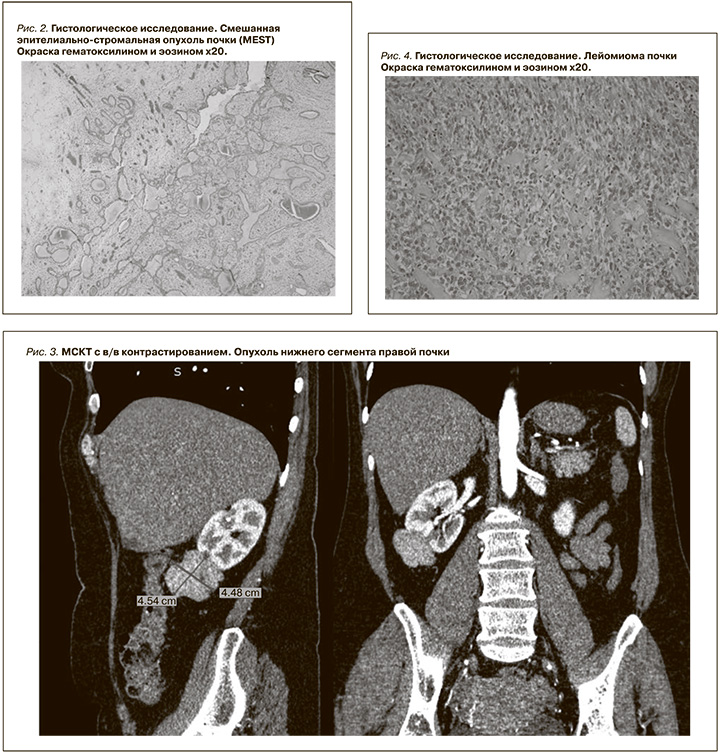

Смешанные эпителиальные стромальные опухоли почек (MEST)

Смешанные эпителиальные стромальные опухоли – MEST (Mixed Epithelial and Stromal Tumour) почки представляют собой редкое подмножество доброкачественных новообразований почек, впервые описанных примерно 20 лет назад. [3]. На сегодняшний день в литературе описано порядка 100 случаев гистологически верифицированных опухолей почек данного типа [4]. Эти образования, обычно появляющиеся у женщин в пери- и постменопаузе, характеризуются двухфазным сóлидным и кистозным составом с вариабельным характером роста. Зачастую радиологическая диагностика данного типа опухоли затруднена ввиду схожести с ПКР и уротелиальным раком собирательной системы почки [4].

С учетом объема и распространенности опухолевого процесса (заинтересованность собирательной системы почки) данное образование клинико-инструментально трактовано как уротелиальный рак собирательной системы почки. В связи с некупируемой консервативно макрогематурией пациентке в экстренном порядке выполнена лапароскопическая нефроретерэктомия справа с резекцией мочевого пузыря с устьем правого мочеточника. Время оперативного пособия составило 128 минут, кровопотеря – 100 мл. Послеоперационный период протекал без осложнений, пациентка выписана из стационара на 4-е сутки после операции. По данным гистологического исследования, фрагменты ткани почки с ростом опухоли двухкомпонентного строения, первый и преобладающий компонент представлен фиброзной стромой с наличием веретеновидных клеток с трудноразличимыми ядрышками, умеренной эозинофильной цитоплазмой.

В строме выявлены обширные фокусы гиалиноза и участки миксоматозной трансформации. Второй компонент представлен «зажатыми» железистыми структурами. Структуры выстланы эпителием, преимущественно кубического типа с округлыми, базально расположенными ядрами и обильной эозинофильной цитоплазмой. Опухоль врастает в почечный синус. Заключение: смешанная эпителиально-стромальная опухоль почки (MEST, рис. 2).

Лейомиома почки

Лейомиома почки – редкая доброкачественная мезенхимальная опухоль, встречающаяся в 0,3% среди всех пролеченных образований почек. В большинстве случаев выявляется случайно без какой-либо клинической симптоматики [5, 6], чаще встречается у женщин (66% всех известных случаев) старше 50 лет . Типичными радиологическими признаками лейомиомы почки являются следующие КТ-критерии: четкие границы, периферическое расположение, однородное накопление контрастного препарата, также опухоль может иметь участки кровоизлияний или кистозной дегенерации при крупных размерах [6].

Клинический случай 2

Пациентка С. 42 лет госпитализирована в стационар в плановом порядке. По данным МСКТ, с в/в контрастированием (рис. 3) определяется экстраренальное образование нижнего сегмента почки размером 45×45×60 мм, активно неоднородно накапливающее контрастный препарат (от 40 до 120 HU).

В плановом порядке пациентке выполнена лапароскопическая резекция правой почки с опухолью, время оперативного лечения составило 140 минут, время ишемии – 24 минуты, кровопотеря – 150 мл. Послеоперационный период протекал без осложнений, пациентка выписана из стационара на 5-е сутки после операции. По данным гистологического и иммуногистохимического исследований, во фрагментах ткани почки рост опухоли из гладкомышечных клеток с выраженно полиморфными веретеновидными ядрами, обильной эозинофильной цитоплазмой, SMA, Calponin – диффузная выраженная цитоплазматическая реакция в опухолевых клетках, CD34, Desmin, HMB45 – отсутствие реакции. Таким образом, иммунофенотип опухоли соответствует лейомиоме (рис. 4, 5).